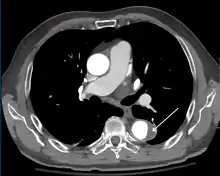

Computed tomography

Computed tomography angiography is a fast, non-invasive test that gives an accurate three-dimensional view of the aorta. These images are produced by taking rapid, thin-cut slices of the chest and abdomen, and combining them in the computer to create cross-sectional slices. To delineate the aorta to the accuracy necessary to make the proper diagnosis, an iodinated contrast material is injected into a peripheral vein. Contrast is injected and the scan performed using a bolus tracking method. This type of scan is timed to injection to capture the contrast as it enters the aorta. The scan then follows the contrast as it flows through the vessel. It has a sensitivity of 96 to 100% and a specificity of 96 to 100%. Disadvantages include the need for iodinated contrast material and the inability to diagnose the site of the intimal tear.

CT with contrast demonstrating aneurysmal dilation and a dissection of the ascending aorta (type A Stanford)

Chest CT with descending (type B Stanford) aortic dissection (red circle)

Type A dissection with pericardial effusion as a result.